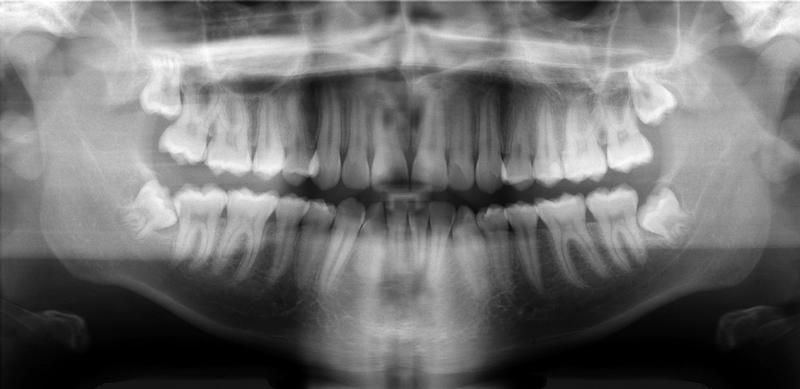

We take detailed 3D images of your mouth & jaw, using Dr. Riman's world-class technology to revitalize your smile – and lifestyle.

He'll give you a visual dental exam, discuss your smile goals, take 3D x-rays, and give you a mystery gift in 3D!